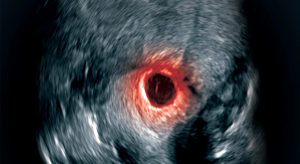

How to diagnose and treat cesarean scar pregnancy

CSP is a challenge but management is possible with a multidisciplinary approach.